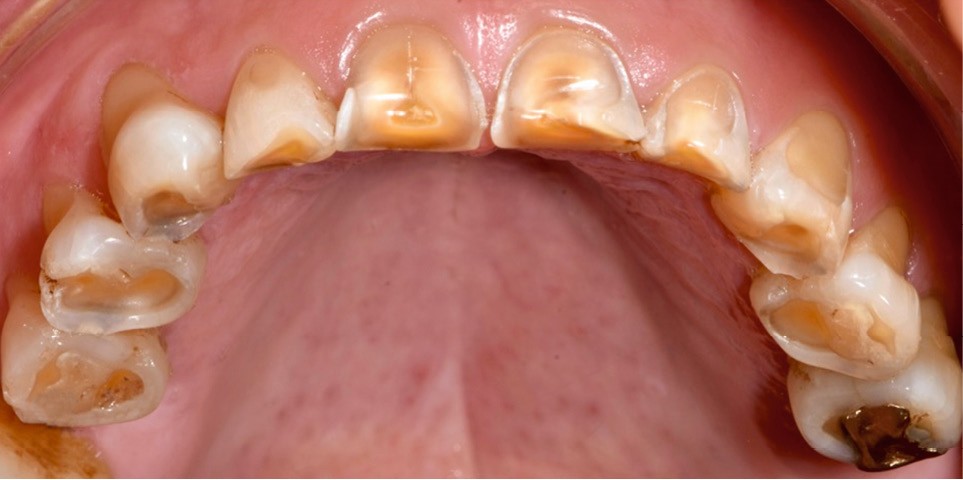

Le cas clinique présenté ici illustre cette démarche thérapeutique. À la suite d’un diagnostic de cancer des voies aérodigestives supérieures, un patient de 68 ans a bénéficié d’un traitement par radiothérapie cervico-faciale, terminée depuis plus de 2 ans. Il souhaite désormais retrouver une réhabilitation fonctionnelle et esthétique de sa cavité orale. Il indique que le délabrement de ses dents antérieures est à l’origine d’un important préjudice esthétique, qui l’a conduit à ne plus sourire. De plus, ses dents absentes réduisent fortement ses capacités masticatoires. Ces différents facteurs influent donc directement son estime de soi et sa qualité de vie, paramètres clés de la rémission dans le cadre oncologique. À l’examen clinique, il présente une perte de calage postérieur, avec des édentements terminaux secteur 2 et 4, ainsi que de volumineuses pertes de substance au niveau des dents présentes (fig. 1).